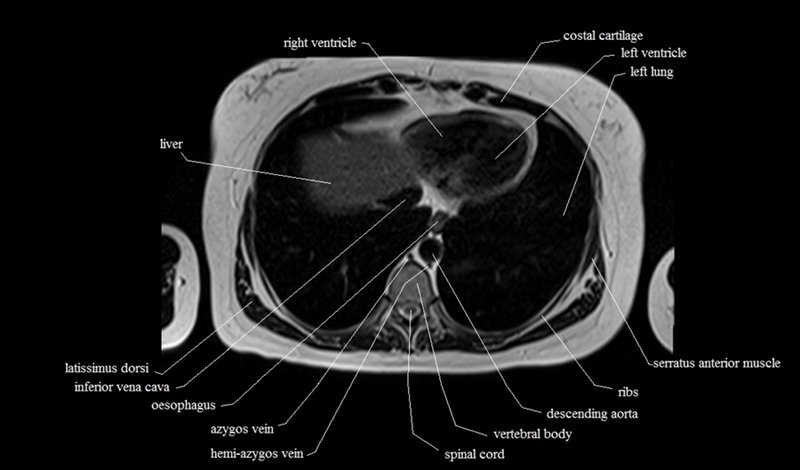

MRI Axial Cross Sectional Anatomy of Chest

This MRI chest (thorax) axial cross sectional anatomy tool is absolutely free to use. Use the mouse scroll wheel to move the images up and down, or alternatively, use the tiny arrows (→) on both sides of the image to navigate through the images. For a more detailed view, double-click the image to view it in full screen, and use the menu in the top right-hand corner to view individual slides or play them in a loop.